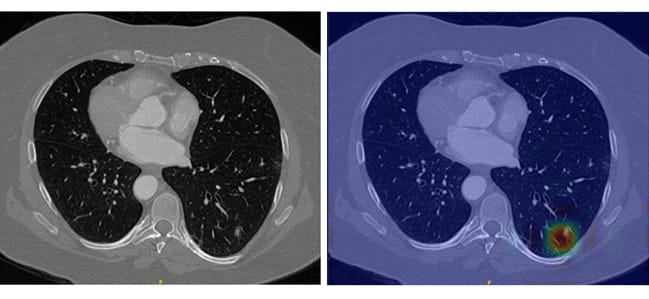

Lung nodules in an unaltered CT scan require sharp eyes for detection (left), but LungWeb highlights suspicious areas to make detection much less labor intensive (right).